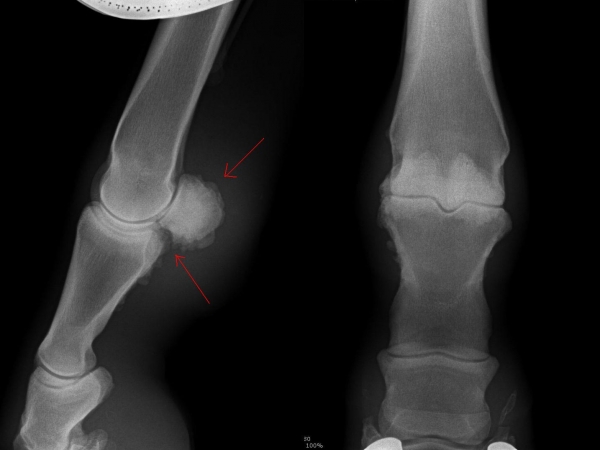

rentgenologické vyšetření

Fragment na spěnkové kosti